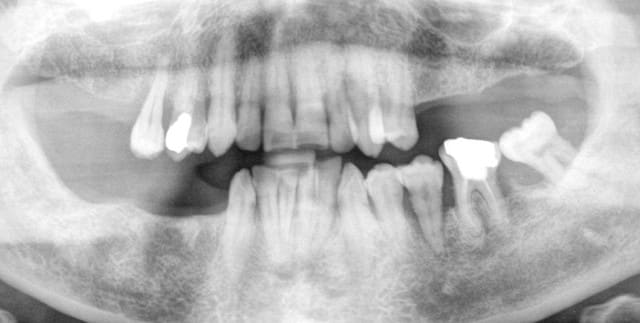

allez, encore un petit cas , de A à Z. à tous les omni réfractaires aux implants: sur un cas comme celui là, vous encaissez le prix d'une céram pour 15 min de travail.

Pour mettre l'eau à la bouche, la pano du tout début, et si tu as deux minutes, dis-moi ce que tu aurais fait

Pour information, 45 ans, motivée, poches paro de 12 mm entre 33 et 32, de 6 mm autour 15, 35 mobile avec poche purulente, j'ai viré la 38.

waou, même ps besoin de greffe, y a qu'au luxembourg qu'on trouve ça. je t'avoue que pour moi, c'est un cas à onze implants, mais c'est toi qui as vu le patient. 3 et 3 en haut, 4 en bas à droite et 1 en bas gauche. à +